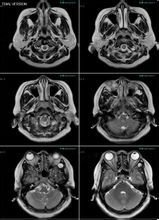

鼻咽部ct軸位平掃(層厚、層距均為5mm),圖像如下:

起源於翼內板,翼突上頜裂和蝶齶孔,主要累及篩竇,蝶竇和顱底。

腫塊引起翼齶窩擴大,壓迫上頜竇後壁,使其彎曲,變形,並向前移位是本病的特徵性表現。

增強呈均勻一致強化。

結果:(華中科技大學同濟醫學院附屬同濟醫院)術後病理診斷:纖維血管瘤。